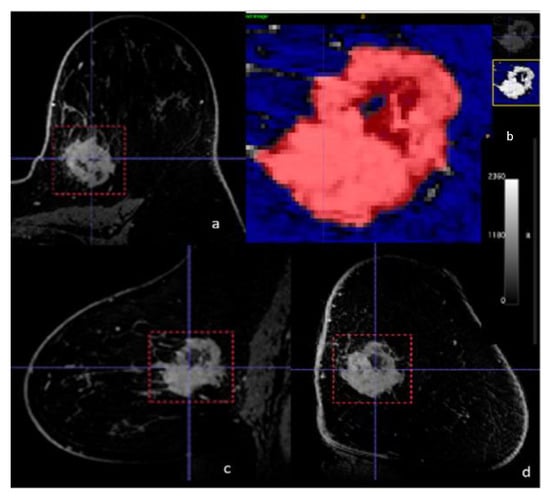

2.5. Radiomics Analysis

3.2. Radiomics Analysis and ML